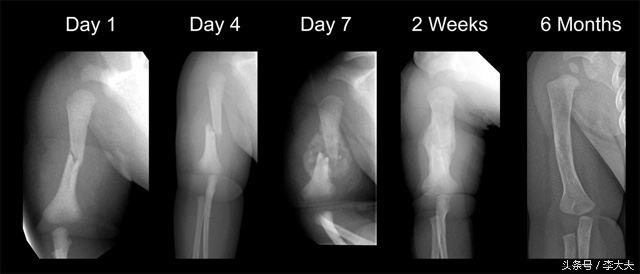

骨折愈合X线片表现

这是骨折的II期愈合情况,I期愈合最理想,但是临床较难实现,这里不做扩展解释。

原始骨痂形成期

一般需要4-8周。

骨内外膜增生,新生血管长入,成骨细胞大量增生,合成并分泌骨基质,骨折端附件内、外形成骨样组织逐渐骨化,形成新骨。骨痂不断强化,当达到足以抵抗肌收缩及剪力和旋转时,则骨折达到临床愈合。这时候X线片商可见骨折处有梭形骨痂阴影,但是骨折线仍隐约可以看到。

骨板成形塑形期

这一过程需8-12周。

原始骨痂中的新生骨小梁逐渐增粗,排列逐渐规则和致密。骨折端的坏死骨经破骨合成骨细胞的侵入,完成死骨清除和新骨形成的爬行替代过程。原始骨痂被板层骨替代,骨折部位形成坚强的骨性连接。